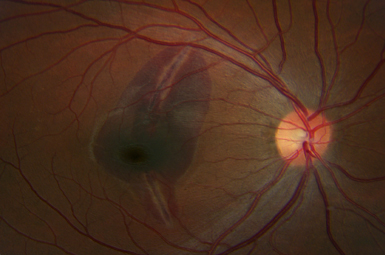

Macular Degeneration

There are two types of Macular Degeneration – Wet and Dry. If it becomes Wet, early intervention can usually preserve sight.

Image courtesy of Carl Zeiss Meditec, Inc.